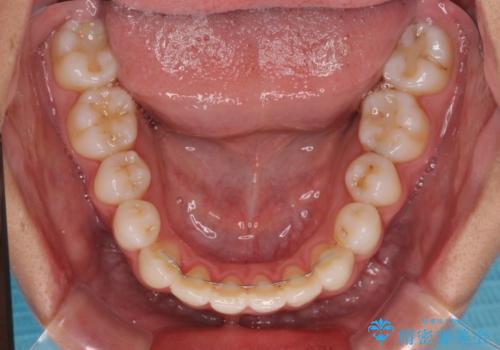

- 前歯のデコボコと奥歯の咬み合わせを気にして来院された患者様です。

右側の奥歯は、上が外側に転位した鋏状咬合を呈しており、前歯のデコボコ改善と並行して咬み合わせを改善していく必要がありました。

装置はワイヤー装置でもインビザラインのマウスピースでもどちらでも適用でしたが、自己管理の煩わしさを嫌い、ワイヤー矯正にて治療を行うこととしました。

ワイヤー矯正を選択されたため、鋏状咬合を確実に改善するために補助装置を併用することとしました。

ワイヤー装置でもマウスピースでも、どちらでも適用の症例でしたが、片側の鋏状咬合はマウスピース矯正ではしっかりと改善できる可能性が低いことや、何と言っても自己管理の煩わしさがないことから、ワイヤー装置を選択されました。